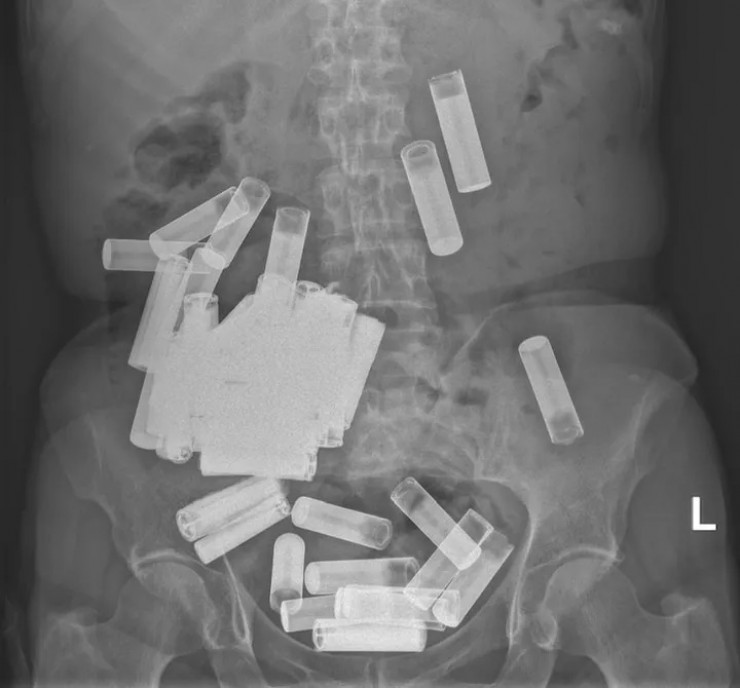

Врачи извлекли 55 батареек из желудка женщины Фото: Irish Medical Journal

В Ирландии врачи вытащили из желудка и толстой кишки 66-летней пациентки 55 пальчиковых батареек, передает Tengrinews.kz со ссылкой на HuffPost.

Сначала медики решили подождать, пока инородные предметы выйдут из организма естественным путем, но спустя неделю тело покинули всего пять батареек, а боль в животе пациентки усилилась. Тогда врачи решили прооперировать женщину и извлекли из нее еще 50 пальчиковых батареек.

"Насколько нам известно, этот случай представляет собой самое большое зарегистрированное количество батареек, проглоченных в один момент времени", - говорится в статье.